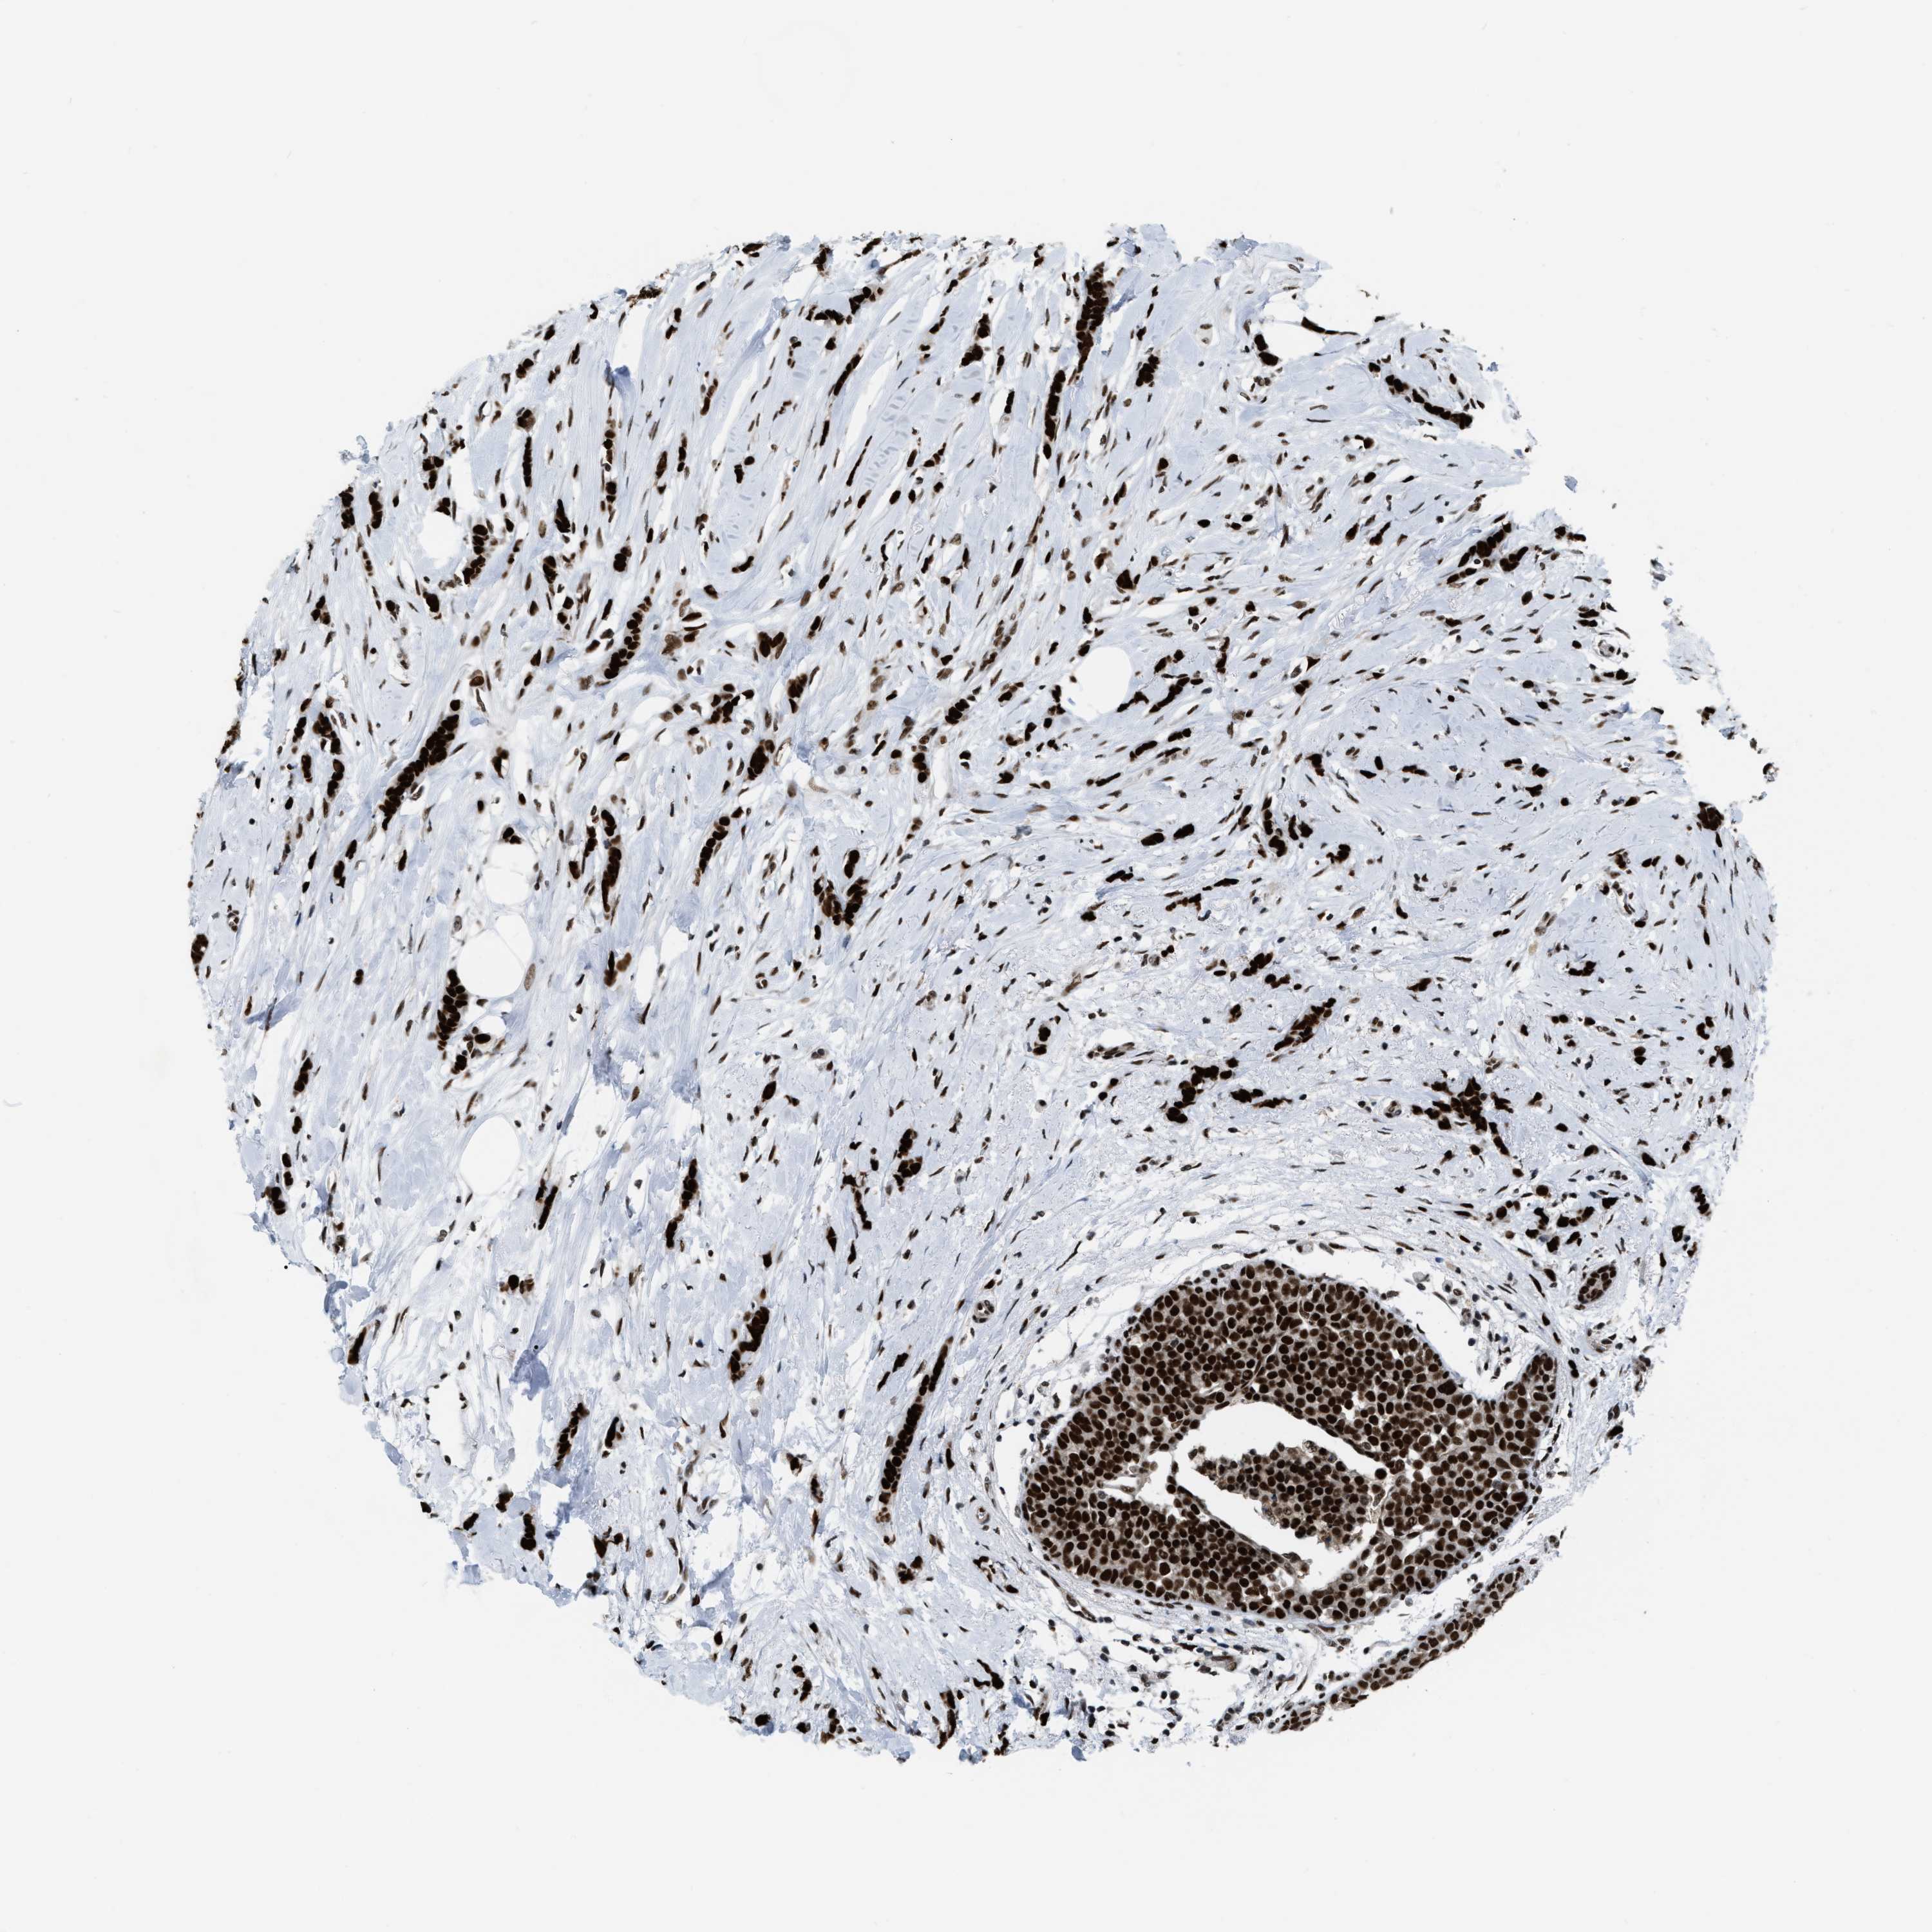

CANCER BREAST CANCER Show tissue menu

BRCA TCGA BRCA VALIDATION PROTEIN EXPRESSION

ANTIBODIES

AND

VALIDATION